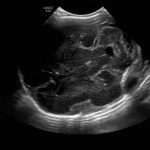

Age: 4 days (born at 24 weeks)

Sex: Male

Indication: Evaluate for germinal matrix hemorrhage

Grade 2 germinal matrix hemorrhage

Sample ReportLeft germinal matrix hemorrhage involving the caudothalamic groove and layering in the occipital horn of the left lateral ventricle without hydrocephalus (grade 2).

No abnormal brain parenchymal echogenicity or extra-axial collections.

Premature sulcation pattern.